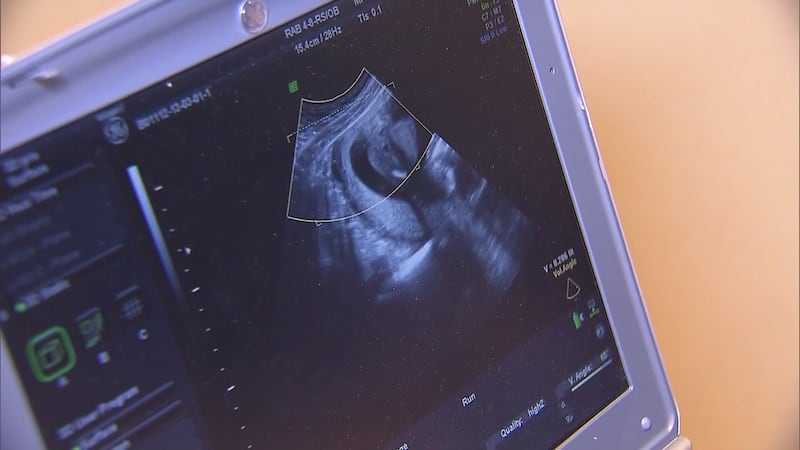

首先得弄清楚啥叫试管婴儿低胎盘位置。正常情况下,胎盘应该附着在子宫体部的前壁、后壁或侧壁。要是胎盘下缘达到或覆盖宫颈内口,其位置低于胎儿先露部,那就被叫做低胎盘位置啦,在医学上也叫前置胎盘。对于通过试管婴儿受孕的准妈妈们来说,由于胚胎着床的特殊性,出现低胎盘位置的概率可能相对高那么一丢丢。